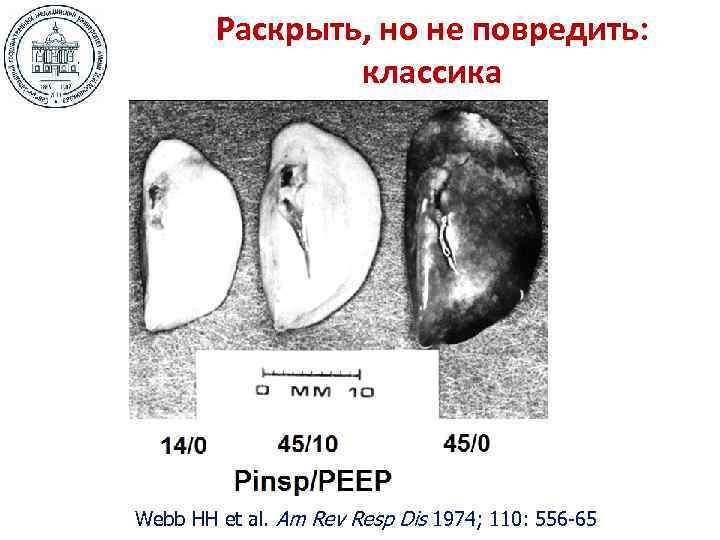

Раскрыть, но не повредить: классика Webb HH et al. Am Rev Resp Dis 1974; 110: 556 -65

Раскрыть, но не повредить: классика Webb HH et al. Am Rev Resp Dis 1974; 110: 556 -65